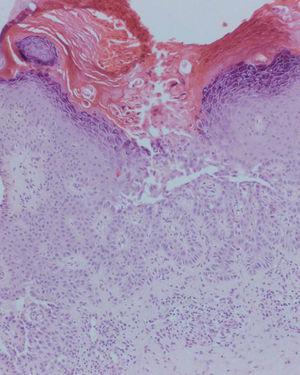

En el estudio histológico de una de las pápulas se apreciaba una acantolisis suprabasal (fig. 2), así como abundantes células disqueratósicas que en las capas superiores de la epidermis tomaban forma de cuerpos redondos y en la capa córnea, de granos de Darier (fig. 3). También presentaba un leve infiltrado inflamatorio linfocitario superficial.

Fig. 3.--Cuerpos redondos y granos de Darier. (Hematoxilina-eosina, x100.)